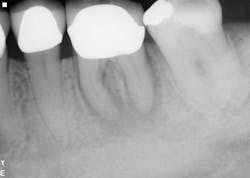

Healing is noted on the six-month follow-up (figure 4).